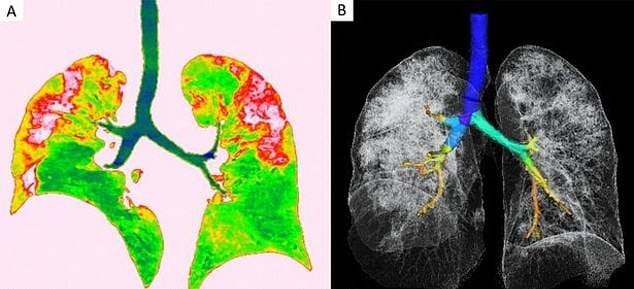

चीन में एक 44 वर्षीय महिला की मौत कोरोना वायरस की वजह से हुई थी. महिला की मौत के बाद जब उसके शरीर का एक्स-रे और सीटी स्कैन किया गया तो दिल दहला देने वाली तस्वीरें सामने आईं.

महिला के शरीर की स्कैन रिपोर्ट रेडियोलॉजिस्ट सोसायटी ऑफ नॉर्थ अमेरिका ने जारी की है. तस्वीरें देखकर ये साफ अंदाजा लगाया जा सकता है कि कोरोना वायरस इंसान के फेफड़ों को कैसे खराब करता है.

फेफड़ों में नीचे की तरफ कॉर्नर में सफेद धब्बे नजर आ रहे हैं. रेडियोलॉजिस्ट की भाषा में इस हिस्से को ग्राउंड ग्लास ओपासिटी कहते हैं, जो इंसान को सांस भरने में मदद करता है.

फेफड़ों की पहली पिक्चर (ए) और आखिरी पिक्चर (एफ) में आप आसानी से अंतर देख सकते हैं. सफेद रंग के ये धब्बे असल में बलगम है जो फेफड़ों में हवा की जगह भर जाता है. इसके बाद इंसान को सांस लेने में दिक्कत होने लगती है.

ये दूसरी तस्वीर 54 वर्षीय एक अन्य महिला की है. यहां भी तस्वीरें लगभग वैसी ही कहानी बयां कर रही हैं. यह महिला चीन के सिचुआन प्रांत की रहने वाली हैं.